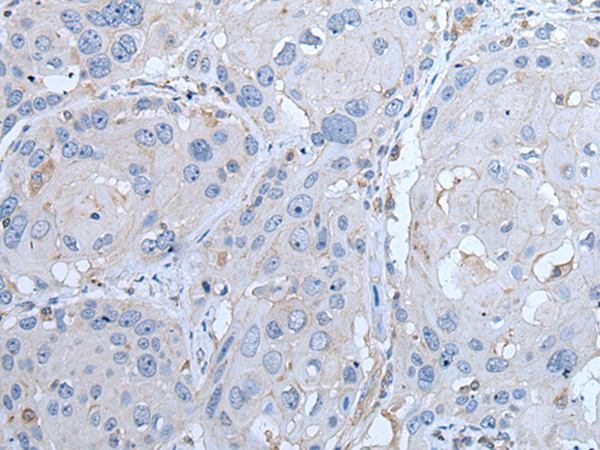

The image on the left is immunohistochemistry of paraffin-embedded Human esophagus cancer tissue using(LTBP4 Antibody) at dilution 1/35

,

The image on the left is immunohistochemistry of paraffin-embedded Human breast cancer tissue using (LTBP4 Antibody) at dilution 1/35